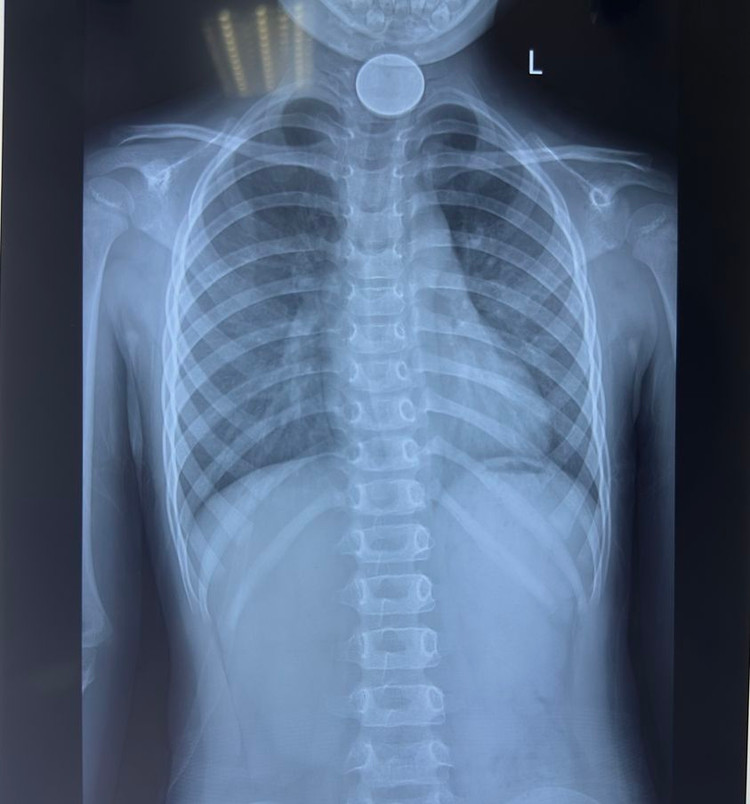

Sau khi vào viện, cháu bé được thăm khám và chụp X-quang. Kết quả cho thấy có một dị vật hình tròn đường kính 3cm bằng kim loại nằm giữa thực quản.

| Bé 4 tuổi bị dị vật đồng xu nằm giữa thực quản |

Các bác sĩ đã gắp thành công một đồng xu kim loại có hình tròn đường kính 3cm từ trong thực quản cháu bé ra ngoài. Sau thủ thuật, bệnh nhi đã hồi tỉnh và trở lại sinh hoạt bình thường, không còn đau, không có biến chứng.